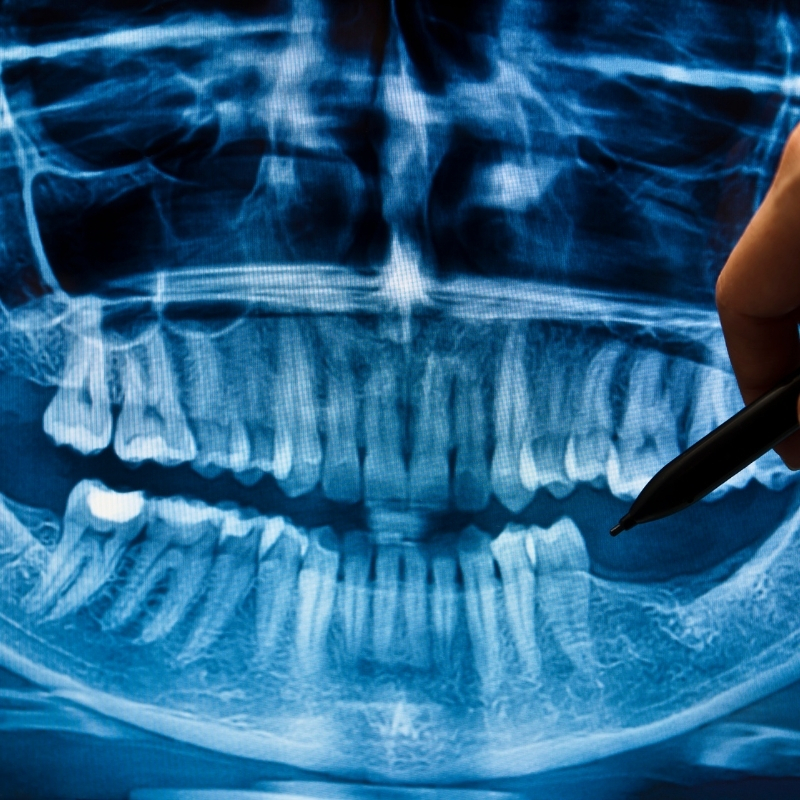

RTG snímky

Röntgen alebo skrátene RTG vyšetrenie by malo byť súčasťou každej preventívnej prehliadky u stomatológa. Nie všetky problémy ústnej dutiny a chrupu možno totiž spozorovať voľným okom, a to aj napriek tomu, že ono „jednoduché oko“ patrí v tomto prípade špecialistovi v odbore. Röntgen je preto skvelým pomocníkom, ktorý pomôže odhaliť skryté nedostatky rôzneho charakteru.

Výsledkom RTG zubov je snímka pevných tkanív v oblasti ústnej dutiny, z ktorej vie zubný lekár vyčítať široké spektrum rôznych skrytých problémov. Od medzizubných kazov, cez kazy ukryté pod zubnou výplňou až po nálezy na koreňoch zubov, a to všetko je len začiatok. Okrem toho vie röntgen upozorniť na zvláštne anomálie či hroziace choroby, napríklad cysty. Takáto snímka zobrazí aj tie zuby, ktoré sa ešte neprerezali. U malých pacientov to môžu byť zuby trvalé, u dospelých zase zuby múdrosti alebo nadpočetné zuby, ktoré dokážu človeka pekne potrápiť.

U nás v Dental-Centre využívame v oblasti RTG inovatívnu digitálnu technológiu. Vďaka nej je robenie snímok záležitosťou niekoľkých sekúnd a pacientovi sa dostáva podstatne menej škodlivého žiarenia ako pri klasickom röntgene. Digitálny systém zachytenia RTG žiarenia nám umožňuje tvorbu kvalitnejších fotografií, ktoré našim lekárom sprostredkujú lepšiu viditeľnosť, a teda následne aj vám podrobnejšie a presnejšie informácie.